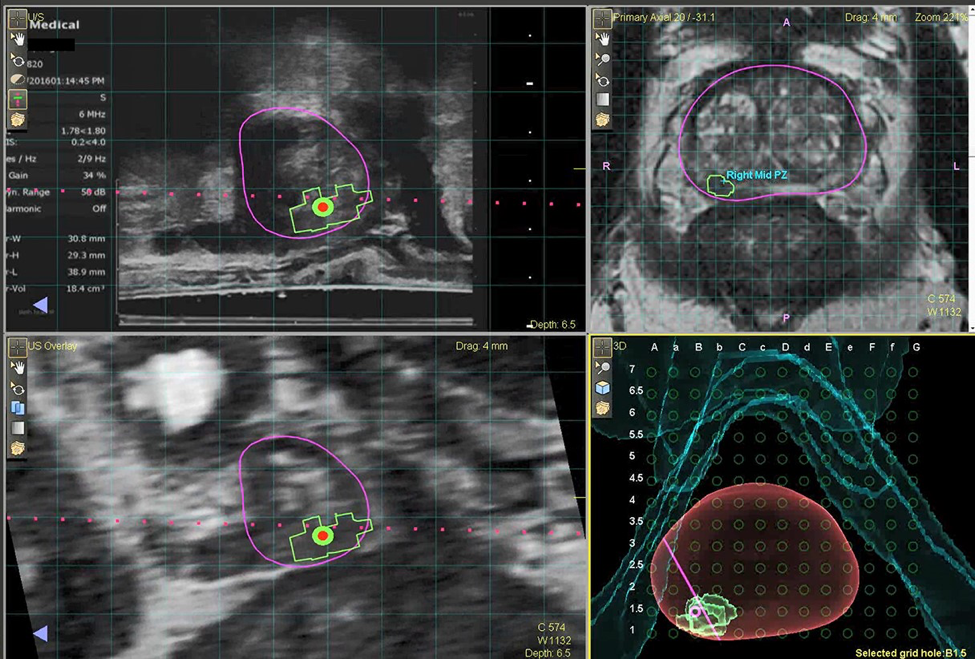

A newer technique, called MRI (Magnetic Resonance Imaging) Fusion Biopsy, involves an MRI performed prior to the biopsy and is more accurate than ultrasound at detecting prostate lesions.

Over the past few years, there has been an increase in the use of Magnetic Resonance Imaging (MRI) to accurately image the prostate with a technique called MRI fusion biopsy.

This procedure involves an MRI performed prior to the biopsy to identify lesions in the prostate which may be cancerous, which can then be overlayed on the live ultrasound at the time of biopsy. This enables the urologist to directly target and biopsy any lesions in the prostate in real time and is considered more accurate than a transrectal ultrasound at detecting prostate lesions and obtaining biopsy results.

An accurate biopsy helps to identify which patients are suitable candidates for prostate cancer treatment or for actively watching the cancer (active surveillance).